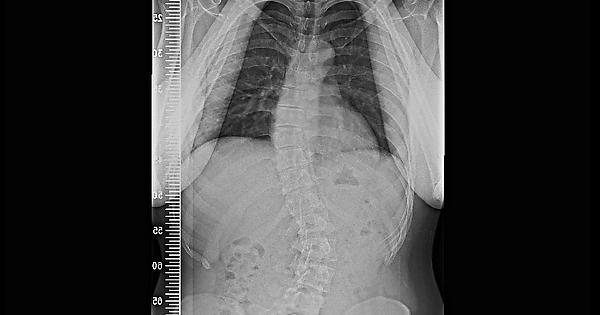

脊椎側彎 脊聲動 健康跟著走

博客來 正解 脊椎側彎的真相 寫給60萬人的自我檢測與矯正法